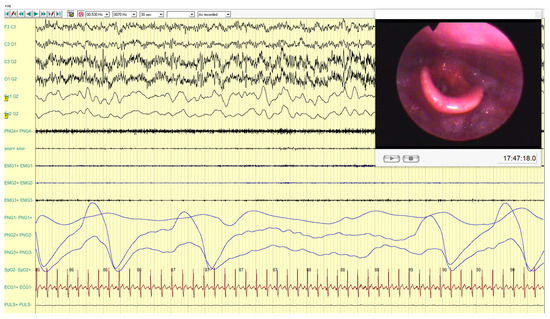

An average BIS value of 45, a minimum of 25, an average SPO2 of 85 and a minimum of 76 are reported. In the male patient, we observed a retropalatal oropharyngeal obstruction site with 100% concentric prolapse and a retrolingual oropharyngeal obstruction site with 75% concentric prolapse. The average 65 and minimum 49 BIS values are reported, and the SPO2 values were 89% the average and 85% the minimum (Figure 4).

Figure 4. The figure shows the presence of obstructive apnea based on respiratory parameters (PNG1, PNG2, PNG3), with associated desaturation (87–89% range) and increased muscles activities on PNG4 (mylohyoid muscle), EMG1 (right masseter muscle) and EMG2 (left masseter muscle).

Figure 8. In this frame, it is possible to observe the persistence of obstructive apnea with desaturation (85–89% range) during the bimanual mandibular advancement maneuver. Furthermore, the persistence of muscle activities on intercostal muscle (EMG3) and on masseter muscles (EMG1, EMG2) is noticeable.